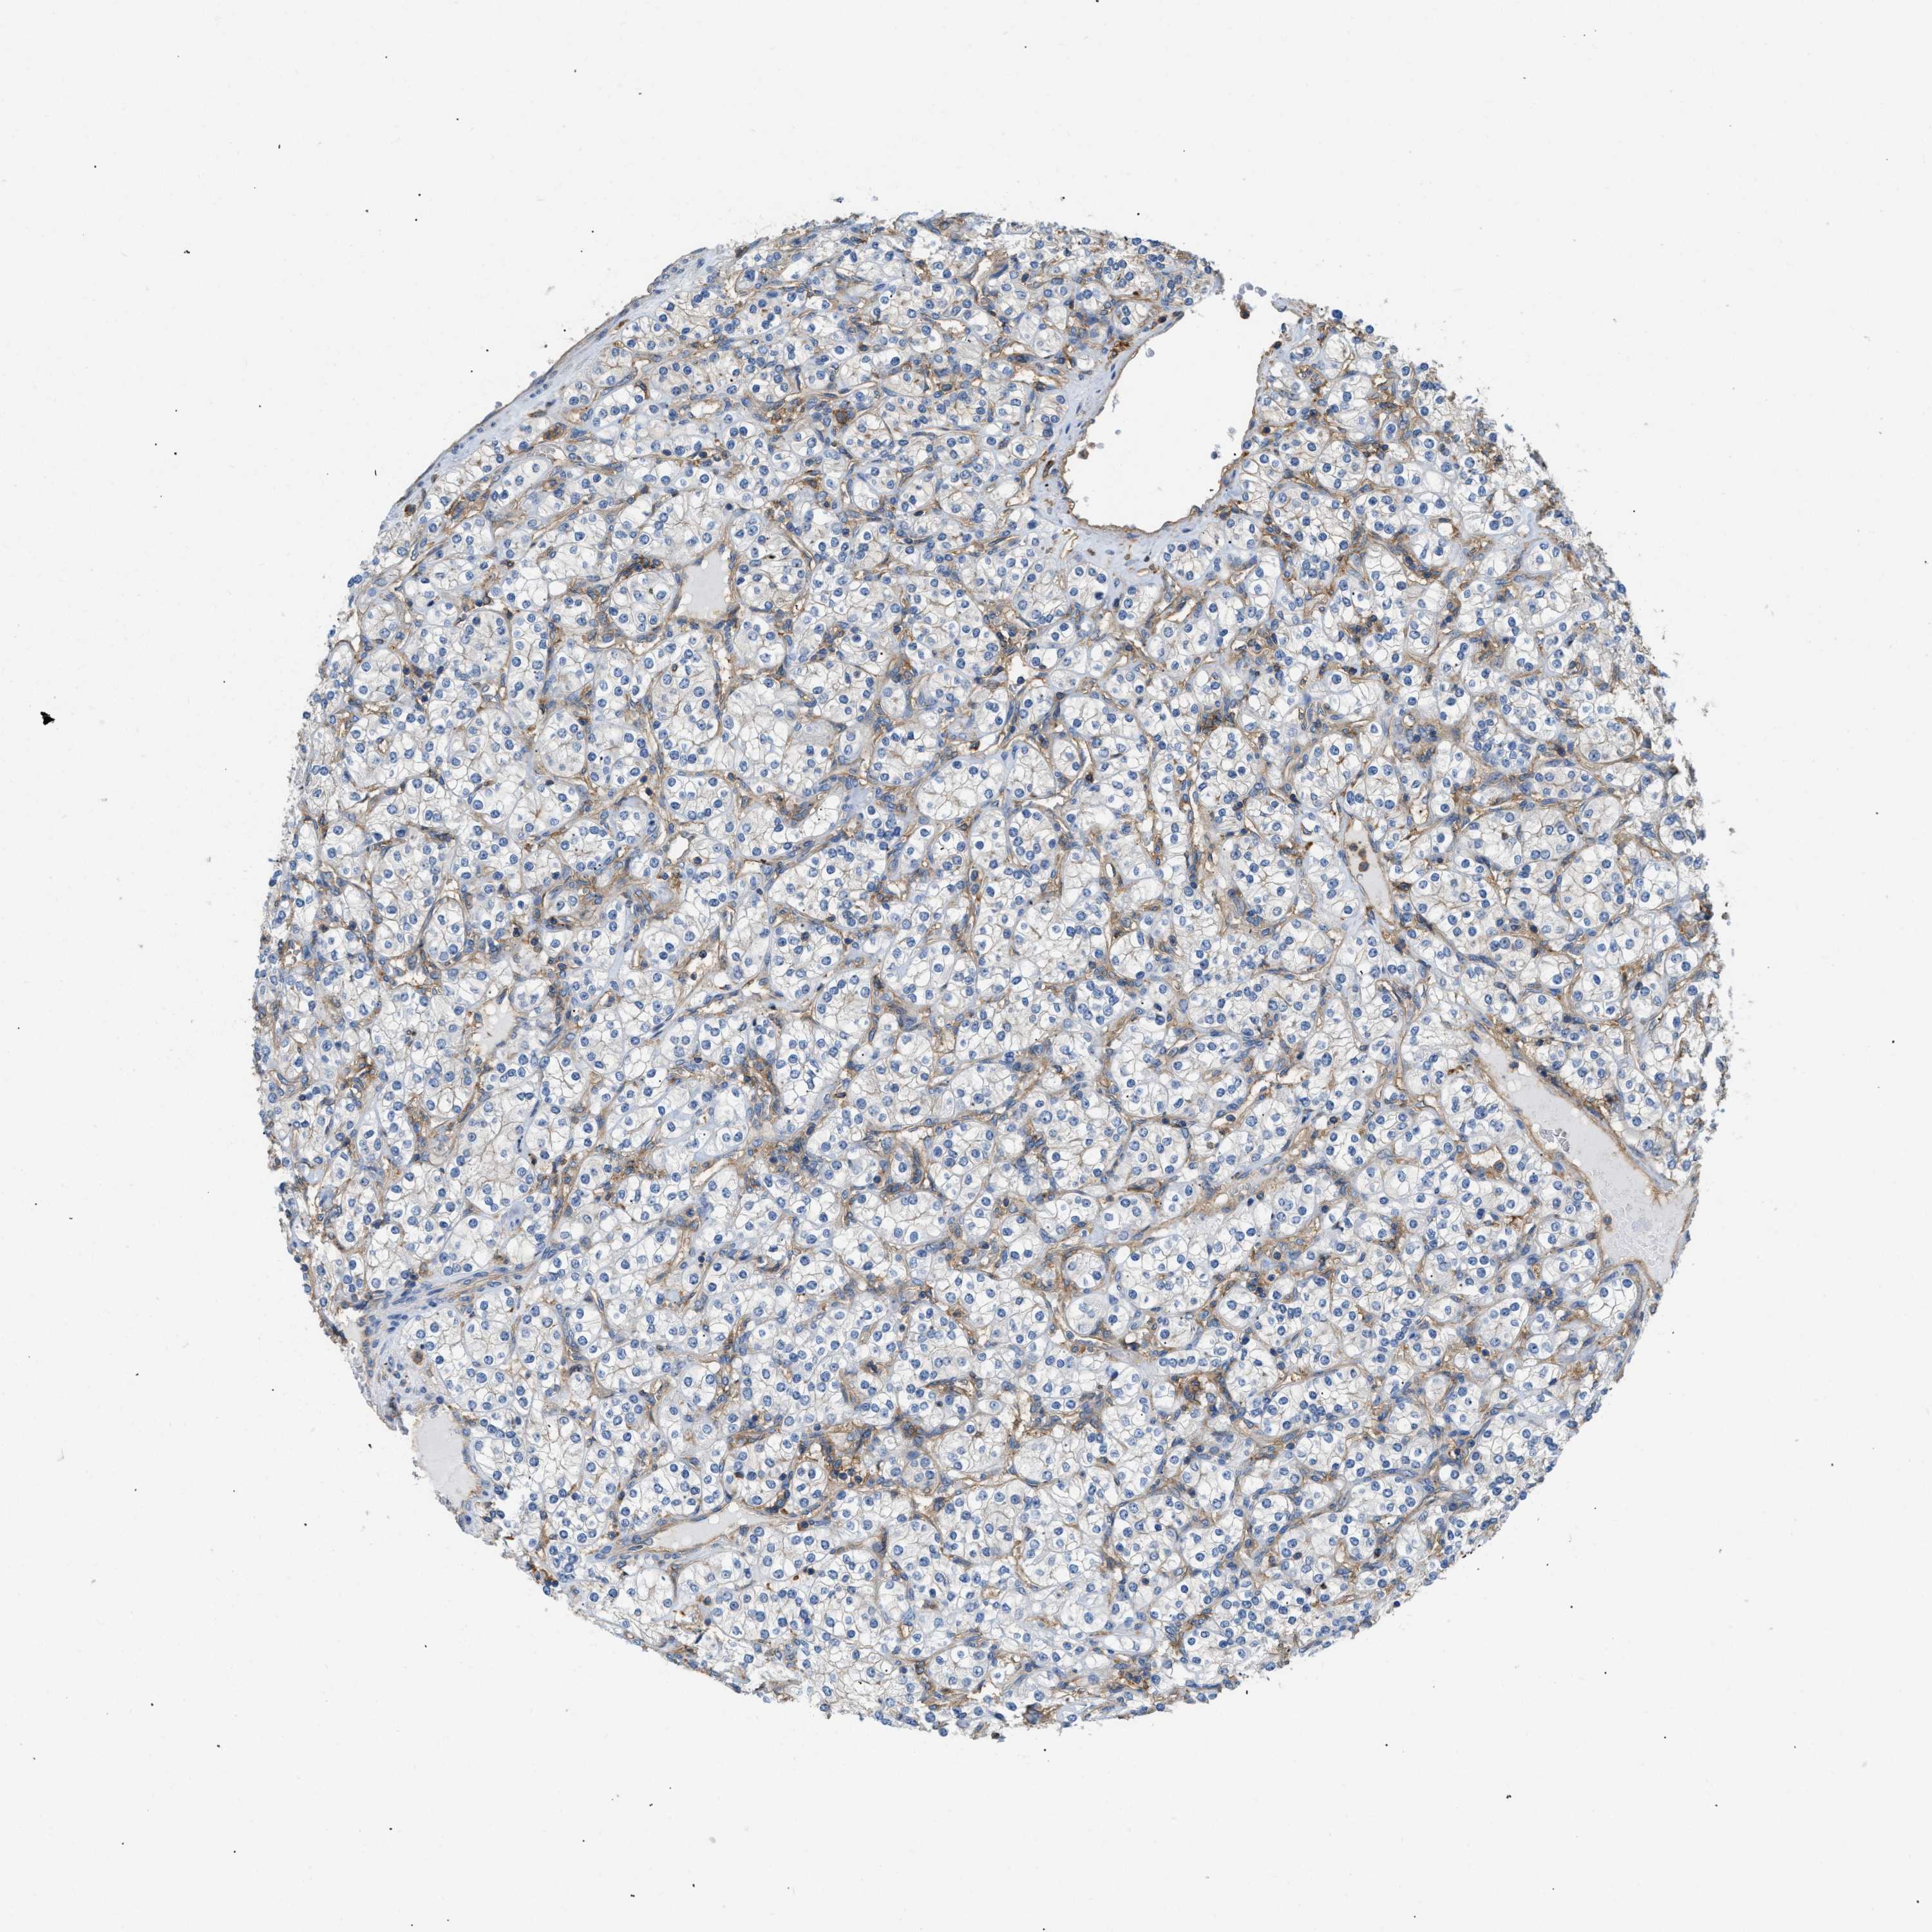

KIDNEY RENAL CLEAR CELL CARCINOMA (VALIDATION) - Interactive survival scatter ploti

The Survival Scatter plot shows the clinical status (i.e. dead or alive) for all individuals in the patient cohort, based on the same data that underlies the corresponding Kaplan-Meier plots. Patients that are alive at last time for follow-up are shown in blue and patients who have died during the study are shown in red.

The x-axis shows the expression levels (FPKM) of the investigated gene in the tumor tissue at the time of diagnosis. The y-axis shows the follow-up time after diagnosis (years). Both axes are complimented with kernel density curves demonstrating the data density over the axes. The top density plot shows the expression levels (FPKM) distribution among dead (red) and alive patients (blue). The right density plot shows the data density of the survived years of dead patients with high and low expression levels respectively, stratified using the cutoff indicated by the vertical dashed line through the Survival Scatter plot. This cutoff is automatically defined based on the FPKM cutoff that minimizes the p-score. The cutoff can be changed by dragging the vertical line or by entering a cutoff value in the square labeled "Current cut-off".

Under the Survival Scatter plot the p-score landscape (black curve; left axis) is shown together with dead median separation (red curve; right axis). Dead median separation is the difference in median mRNA expression between patients who have died with high and low expression, respectively. It is calculated as follows: median FPKM expression of dead patients with high expression - median FPKM expression of dead patients with low expression. This is intended to aid the user in visually exploring custom cutoffs and the associated p-scores and dead median separation.

Individual patient data is displayed and can be filtered by clicking on one or more of the category buttons on the top of the page. Categories describing expression level and patient information include: high, low, alive, dead, female, male and tumor stages. The scale of the x-axis can be toggled between linear and log-scale by clicking on the "x log" button. Mouse-over function shows TCGA ID, patient information and mRNA expression (FPKM) for each patient.

& Survival analysisi

Kaplan-Meier plots summarize results from analysis of correlation between mRNA expression level and patient survival. Patients were divided based on level of expression into one of the two groups "low" (under cut off) or "high" (over cut off). X-axis shows time for survival (years) and y-axis shows the probability of survival, where 1.0 corresponds to 100 percent.

GNB4 is not prognostic in Kidney Renal Clear Cell Carcinoma (validation)

Best expression cut offi

Based on the FPKM value of each gene, patients were classified into two groups and association between prognosis (survival) and gene expression (FPKM) was examined. The best expression cut-off refers the FPKM value that yields maximal difference with regard to survival between the two groups at the lowest log-rank P-value. Best expression cut-off was selected based on survival analysis .

When clicking on this number, the vertical dashed line indicating cut-off, the interactive survival plot, and the Kaplan-Meier curve will be adjusted to show results based on the best expression cut-off.

: 16.77

Median expressioni

Median expression refers to the median FPKM value calculated based on the gene expression (FPKM) data from all patients in this dataset. When clicking on this number, the vertical dashed line indicating cut-off, the interactive survival plot, and the Kaplan-Meier curve will be adjusted to show results based on the median expression.

: N/A

Median follow up timei

Median follow up time refers to the median time (years) after diagnosis with this type of cancer, based on clinical data from all patients in this dataset.

P scorei

Log-rank P value for Kaplan-Meier plot showing results from analysis of correlation between mRNA expression level and patient survival.

N/A

5-year survival highi

5-year survival for patients with higher expression than the expression cutoff.

For melanoma and glioma, 3-year survival is shown.

5-year survival lowi

5-year survival for patients with lower expression than the expression cutoff.

TCGA RNA samplesi

RNA-seq data is reported as average FPKM (number Fragments Per Kilobase of exon per Million reads), generated by the The Cancer Genome Atlas (TCGA) .

Normal distribution across the dataset is visualized with box plots, shown as median and 25th and 75th percentiles. Points are displayed as outliers if they are above or below 1.5 times the interquartile range. FPKM values of the individual samples are presented next to the box plot.

Average pTPM 21.0

Number of samples 100